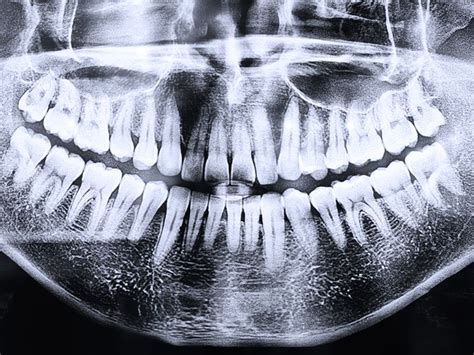

Radiografía Panorámica Dental (Ortopantomografía)

La radiografía panorámica dental, también conocida como ortopantomografía, ofrece una imagen general de la boca, mostrando los maxilares, la mandíbula y los dientes en una sola película. Sin duda la ortopantomografía es el método preferido de los dentistas. Es una herramienta indispensable para un diagnóstico precoz en diversas patologías odontológicas, así como para planificar tratamientos de prótesis, ortodoncias, exodoncias e implantes. Tiene la desventaja en relación con el Tac 3d, que se una radiografía de dos dimensiones, todo lo vemos aplanado. Vemos a lo alto y a lo ancho pero no el grosor.

Precio: El coste de una radiografía panorámica dental puede variar en función de la clínica y el equipo utilizado, pero suele oscilar entre 30€ y 80€.